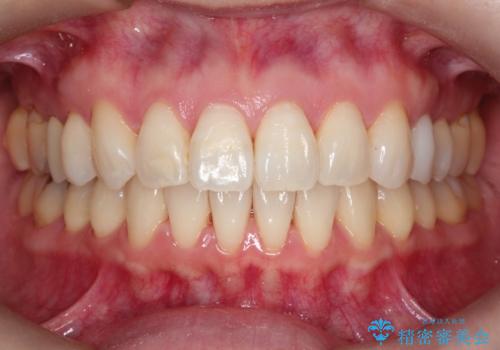

【インビザライン 】前歯を下げたい

- 前歯の凸凹と、前突を主訴に来院されました。

インビザライン にて治療を行なっております。

治療期間中はゴムかけを行なってもらうことで、前歯を下げることができました。